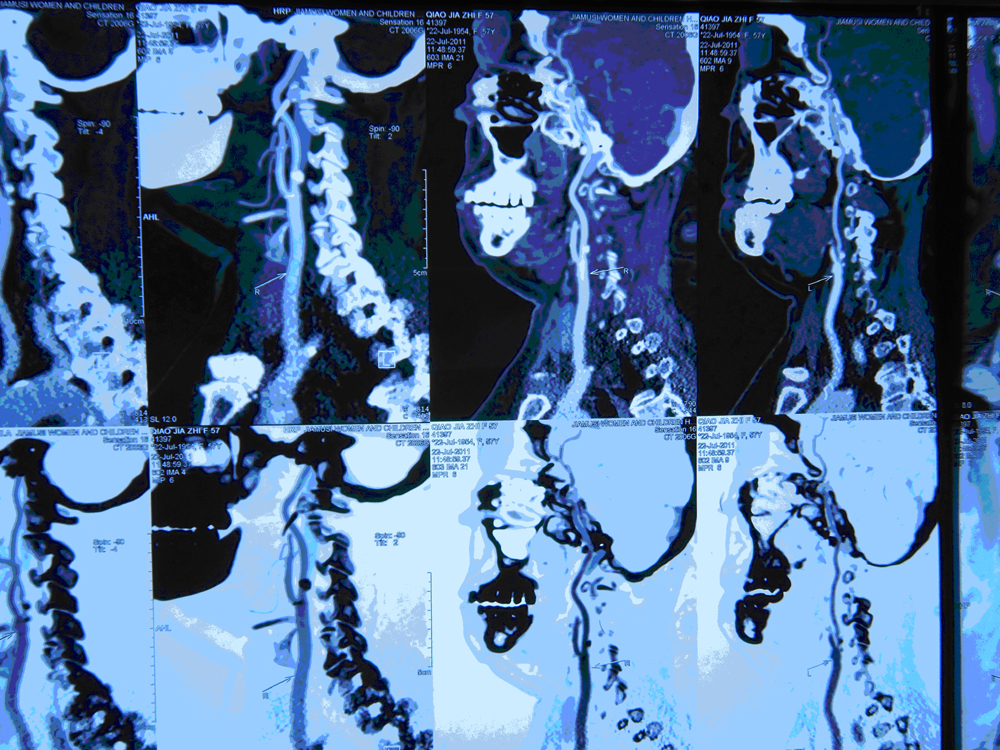

头颈CTA:右侧颈总动脉远段轻度狭窄;右侧颈内动脉起始部轻度狭窄,左侧颈内动脉重度狭窄(75-90%);左侧大脑前动脉A1段发育异常;右椎动脉颅内段轻度、左椎动脉颅内段中-重度狭窄;右侧大脑后动脉P2段中-重度狭窄。

DSA:左颈内动脉80%狭窄     二、初步诊断

患者女性,55岁,主因“发作性左侧偏身麻木无力约5年,头昏约4个月”入院。入院后DSA显示:左侧颈动脉重度狭窄(80%)。于2011年10月31日张勤奕教授于安贞医院行右侧颈内动脉内膜剥脱术,术后患者恢复良好,顺利出院。